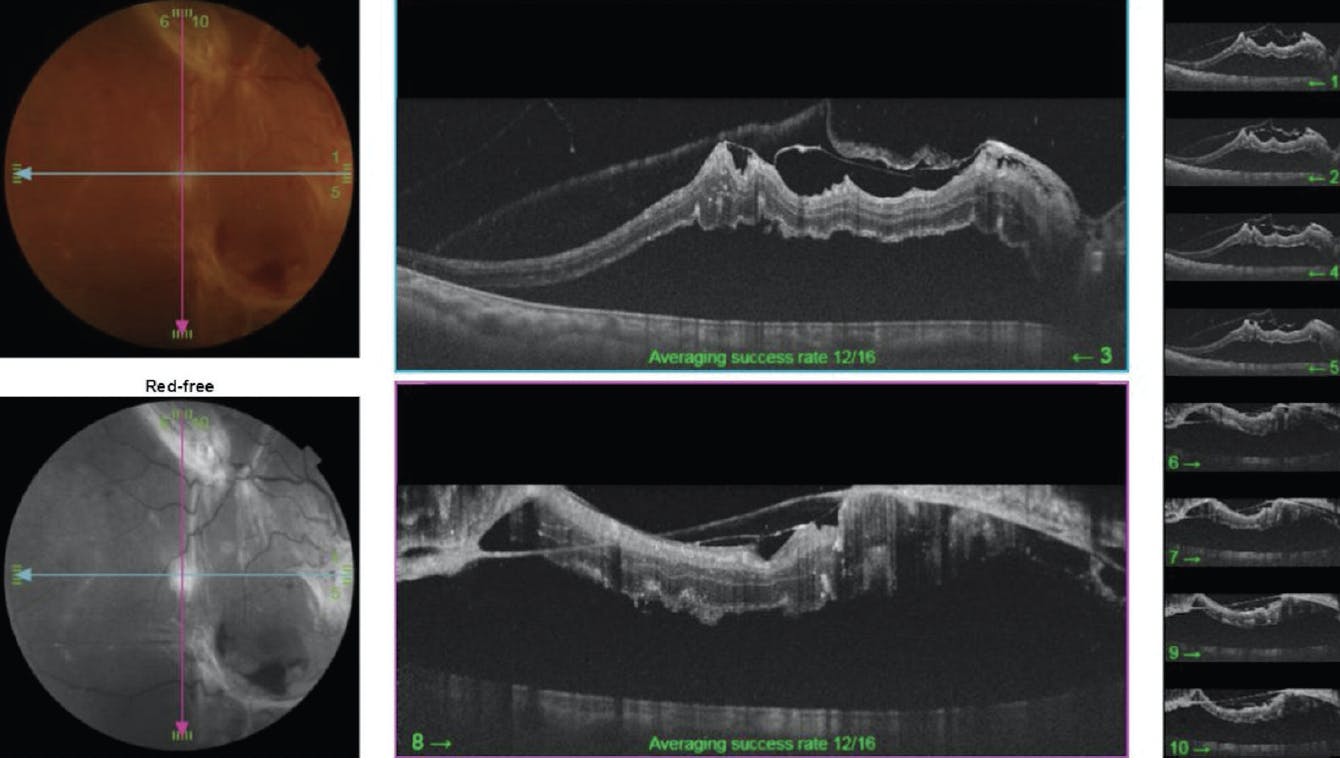

Anterior segment evaluation of both eyes was notable for phakic lenses. Posterior segment examination of the right eye revealed a dense epiretinal membrane (ERM) and a macula-involving TRD in a table-top configuration with attached peripheral retina (Figure 1). Posterior-segment examination of the left eye revealed untreated proliferative diabetic retinopathy with an ERM overlying the macula, but with an attached retina. OCT of the right eye (Figure 2) was notable for incomplete vitreous separation, thick ERM with cystic intraretinal fluid, numerous intraretinal exudates, and neurosensory retinal detachment involving the foveal area. The patient consented to pars plana vitrectomy (PPV), repair of TRD, and silicone oil placement.

Figure 2. Preoperative OCT demonstrating incomplete posterior vitreous separation, thickened posterior hyaloid, ERM, and neurosensory detachment involving fovea.

A second surgery was performed 3 months later to remove silicone oil from the right eye. Upon completion, the retina remained flat (Figure 3). Follow-up OCT (Figure 4) demonstrated interval improvement in the foveal contour with residual outer retinal atrophy. Central VA remained 20/200 with interval progression of cataract. The retina remained attached throughout. Scan the QR code to watch a video of this case.